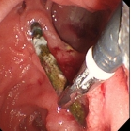

经过详细的多学科讨论后,邱福南主任医师团队最终决定为老张实行胆道镜、胃镜、腹腔镜(三镜)直视下胆总管切开术取出结石及支架,术中探查见支架近端包埋于胆管、远端嵌顿于肠管,难度重重。

幸好肝胆胰医学中心邱福南主任医师与消化内镜中心陈樑主治医师熟练的技艺,让一枚已经满目苍夷的胆管支架时隔八年终于重见天日。术后,老张的腹痛感就消失了,目前已经康复出院。